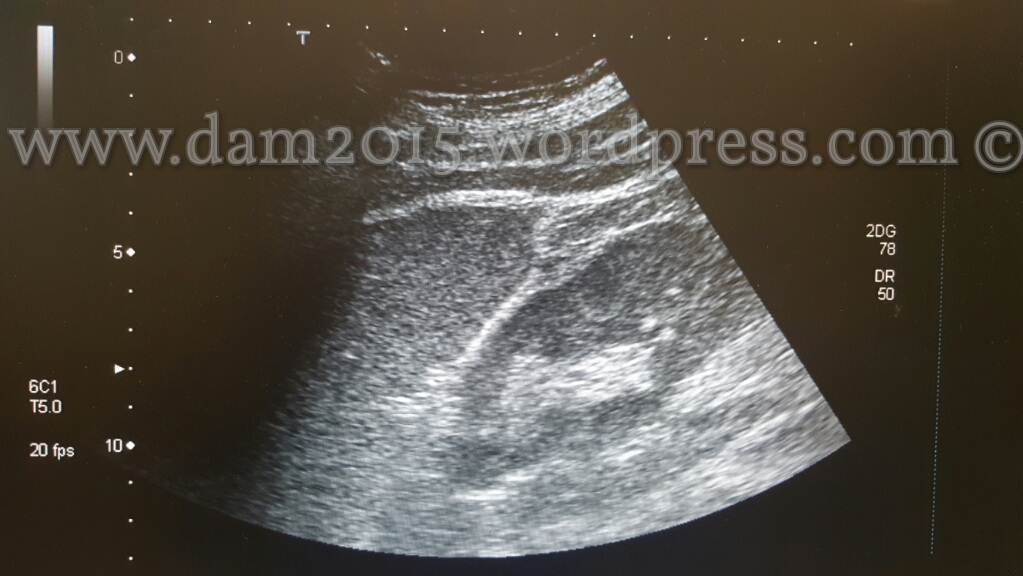

Pz uomo, 56anni.

Incidente stradale moto-auto.

Rottura di milza in due tempi. Emoperitoneo.

Splenectomia.